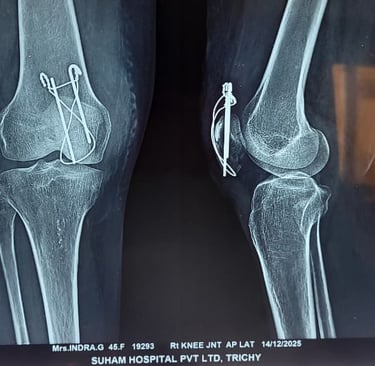

Patella Fracture – Understanding the Injury and Its Treatment

A patella fracture (kneecap fracture) is a common knee injury that usually occurs due to a direct fall on the knee, sports injury, or road traffic accident. The patella plays an important role in the knee extensor mechanism, helping the quadriceps muscle straighten the leg for normal walking and movement.

In some cases, the fracture becomes displaced, meaning the broken bone fragments move apart. A two-part displaced patella fracture disrupts the normal knee function, making it difficult or impossible for the patient to straighten the leg or walk properly.

Such fractures usually require surgical fixation using K-wire and Tension Band Wiring (TBW). This procedure helps to realign the broken fragments, stabilize the bone, and restore the knee’s extensor mechanism, allowing proper healing and recovery.